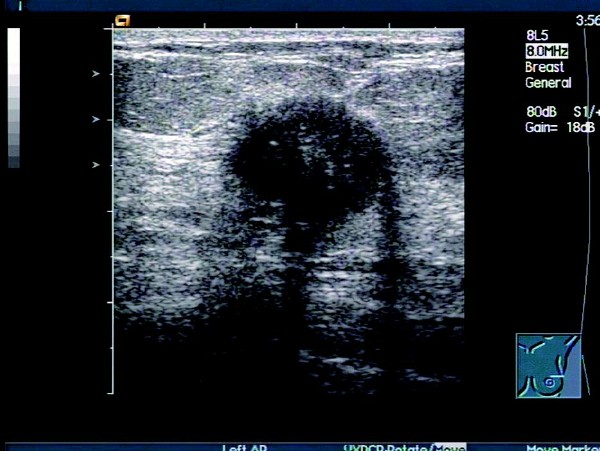

1. 肿块位于乳腺腺体内,边界模糊、不规则,多无包膜,呈浸润状、锯齿状或蟹足状,肿物的前后径大于左右径。

乳腺癌的超声图像表现,早期乳腺癌的超声表现 2. 内部多呈低回声,少数呈等回声或稍强回声,回声不均匀,可以见到不伴声影的点状、簇状和弧形强回声钙化灶;发生出血、坏死时,可出现不规则液性暗区。

乳腺癌的超声图像表现,早期乳腺癌的超声表现 3. 后方回声衰减,在浸润性导管癌和硬癌中比较常见,侵及乳腺后间隙,出现后间隙变薄或消失;侵及肌层,出现肌筋膜连续性中断。但有些少见癌(如单纯癌和髓样癌)中则不一定出现回声衰减,甚至可能会出现后方回声增强的征象。

乳腺癌的超声图像表现,早期乳腺癌的超声表现 4. 部分肿块边缘可出现“恶性晕”征,表现为肿块前壁和侧壁不规则、厚薄不均的强回声带包绕,厚度约 1~3 mm

5.CDFI 显示肿块周边及内部血流信号增多,并有新生血管及动-静脉瘘形成,内见穿支动脉血流,形成高速高阻及动静脉混叠现象。

患者,女,46岁。查体时发现右乳腺一肿物,活动度差,质硬。超声检查报告显示:右侧乳腺外上下象限乳腺边缘可见一大小约1.5 cm×1.2cm的偏低回声团,边界不清晰,形态不规则,包膜不明显。内部回声不均匀,可见少量沙砾样强回声点,纵横比>1,偏低回声团后方衰减明显。CDFI:其内可见短管样血流信息,动脉可见高速,高阻血流信息。

超声提示:右侧乳腺实质性肿块伴钙化,考虑乳腺癌